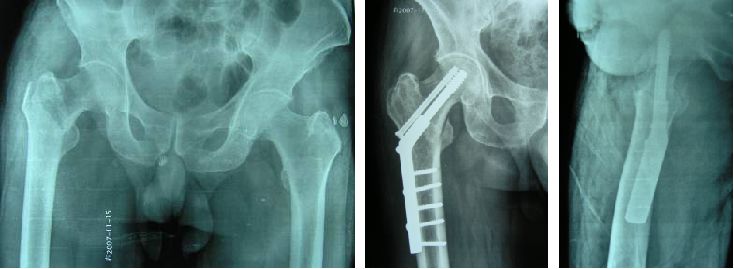

Il a une double fonction de compression et de glisse, avec un effet de compression dynamique et statique.

DCS et plaques de coupe à 95 degrés pour les fractures anticrotales :

Il peut sélectionner correctement le point d'entrée de la vis en fonction de la situation spécifique de la fracture, et l'opération est pratique.

La vis de tension de compression de puissance est à angle droit avec la plaque, ce qui répond aux exigences biomécaniques de la hanche.Lors de la mise en charge, la force négative est d'abord appliquée sur le bras court de la plaque puis dispersée sur chaque vis, de sorte que la contrainte est dispersée et la fixation est exceptionnellement ferme.

Le nombre légèrement supérieur de vis DCS au niveau de la fracture augmente la fermeté et la zone de fracture peut être pontée et fixée, réduisant ainsi l'incidence des complications postopératoires.